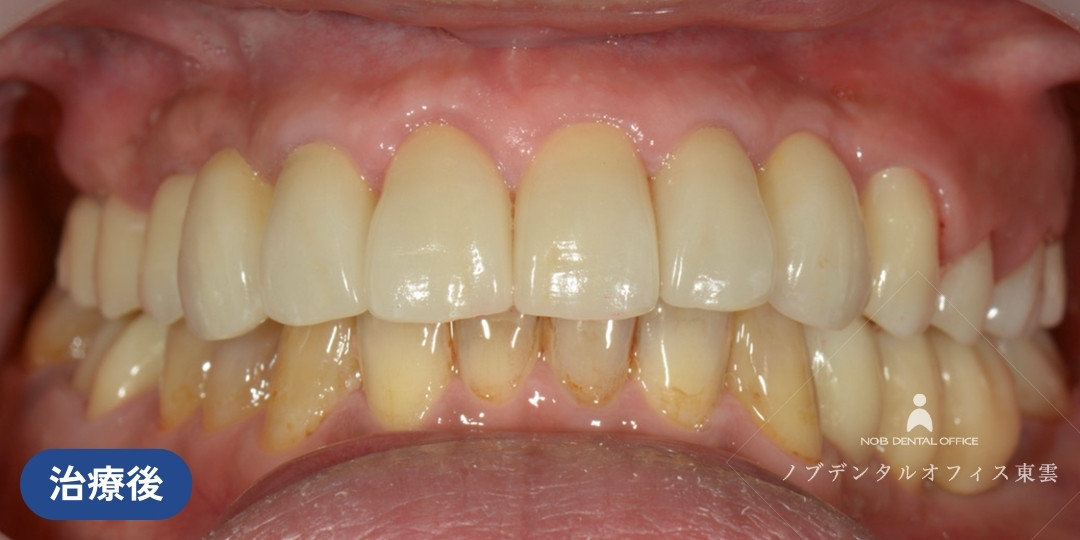

すべての治療が終わった状態です。

セラミッククラウンにてかぶせ物を行いました。

| 期間 | 約3年(仮歯での経過観察を含めて) |

| 費用 | 約500万円 保険適用外 |